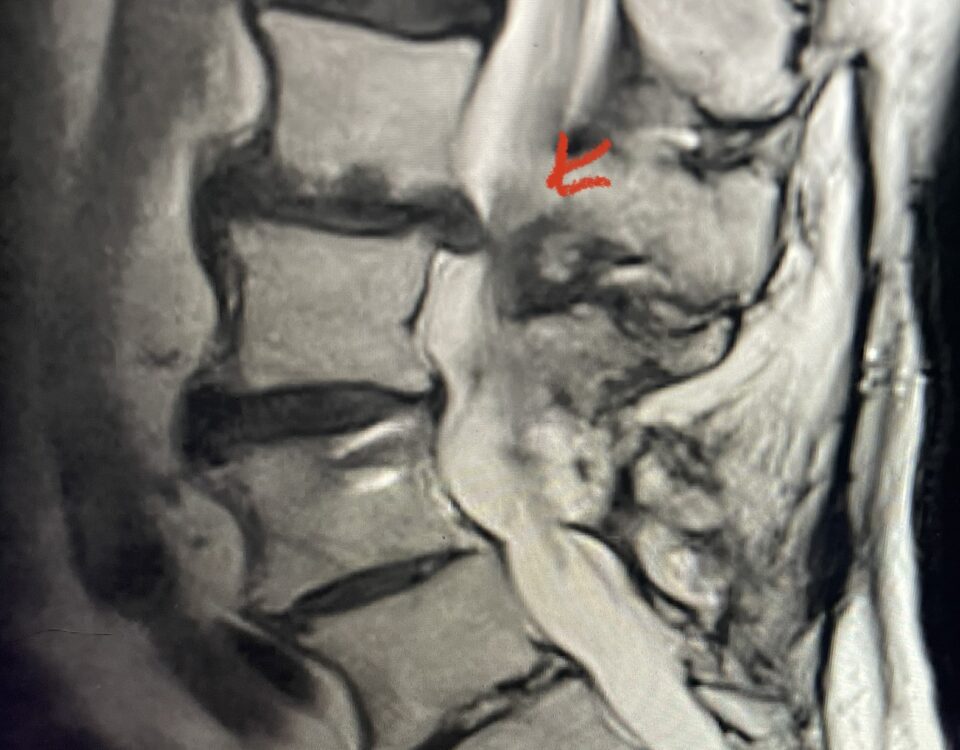

Nervous tissue is soft. The thecal sac is surrounded by a rigid bony ring which forms the spinal canal. Any mass that fills the very small […]

Here is a tough case: This is a 72 year-old male who presented with several months of progressive neck pain without symptoms of the arms or legs. […]